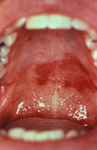

Leucoplasia pilosa oral

Do acervo de Tim Berger, MD, Departamento de Dermatologia da University of California San Francisco; usado com permissão